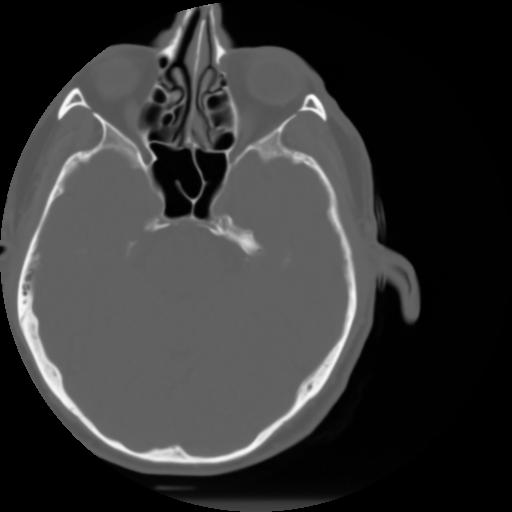

3 CEREBRO,,Axial,3.0,CEREBRO,,